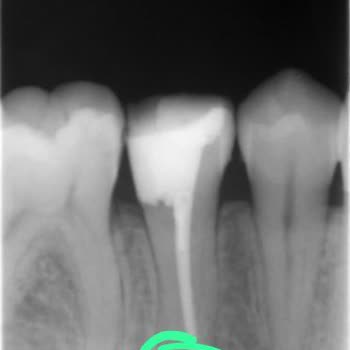

11 Aralık 2025 tarihinde Rize Recep Tayyip Erdoğan Üniversitesi Diş Fakültesi’nde kanal tedavim yapılırken yaşadığım süreci paylaşmak istiyorum. Kanal tedavim doktor Y******* İ**** tarafından iki seansa bölündü. İlk gün bir sorun yaşamazken, ikinci gün gittiğimde dişime anestezi yapılmadı, sadece çok az acıyacağını söyleyerek işleme başladı. Daha sonra başka bir doktor diş kökümde iltihap olduğunu, bu nedenle ağrı olmasının normal olduğunu söyledi.

İşlem sırasında yapılan her şeyi şiddetli bir acıyla hissettim, defalarca canım yandığı için durdurmak zorunda kaldım. Buna rağmen doktor sinirlendi, ağzımı kapatırsam tükürük dolacağını, dayanmak zorunda olduğumu söyledi. Ancak acı o kadar şiddetliydi ki defalarca fenalık geçirecek gibi oldum, hemşireler müdahale etmek zorunda kaldı. Buna rağmen yine beni suçlayarak dayanmak zorunda olduğumu söyledi. Anestezi yapılmadan devam edemeyeceğimi söylediğimde ise iğne yaparsak çok beklersiniz diyerek anestezi yapmadı ve tüm işlemi neredeyse tamamen ağrı içinde yaşattı. Yaklaşık 2 saat süren işlemin yaklaşık 1,5 saatini bu şekilde dayanılmaz bir acıyla geçirdim. Panik atak rahatsızlığım var ve orada resmen bir atak geçiriyordum.

Sonrasında başka bir kadın doktor geldi, anestezimi gayet normal şekilde yaptı ve işlemi sorunsuz, acısız şekilde tamamladı. Madem bu kadar kolayca anestezi ile acısız yapılabiliyordu, başta bu uygulamanın yapılmamasını ve yaşadığım bu ağır ağrıyı, psikolojik olarak yıpratıcı süreci büyük bir sorumsuzluk olarak görüyorum.